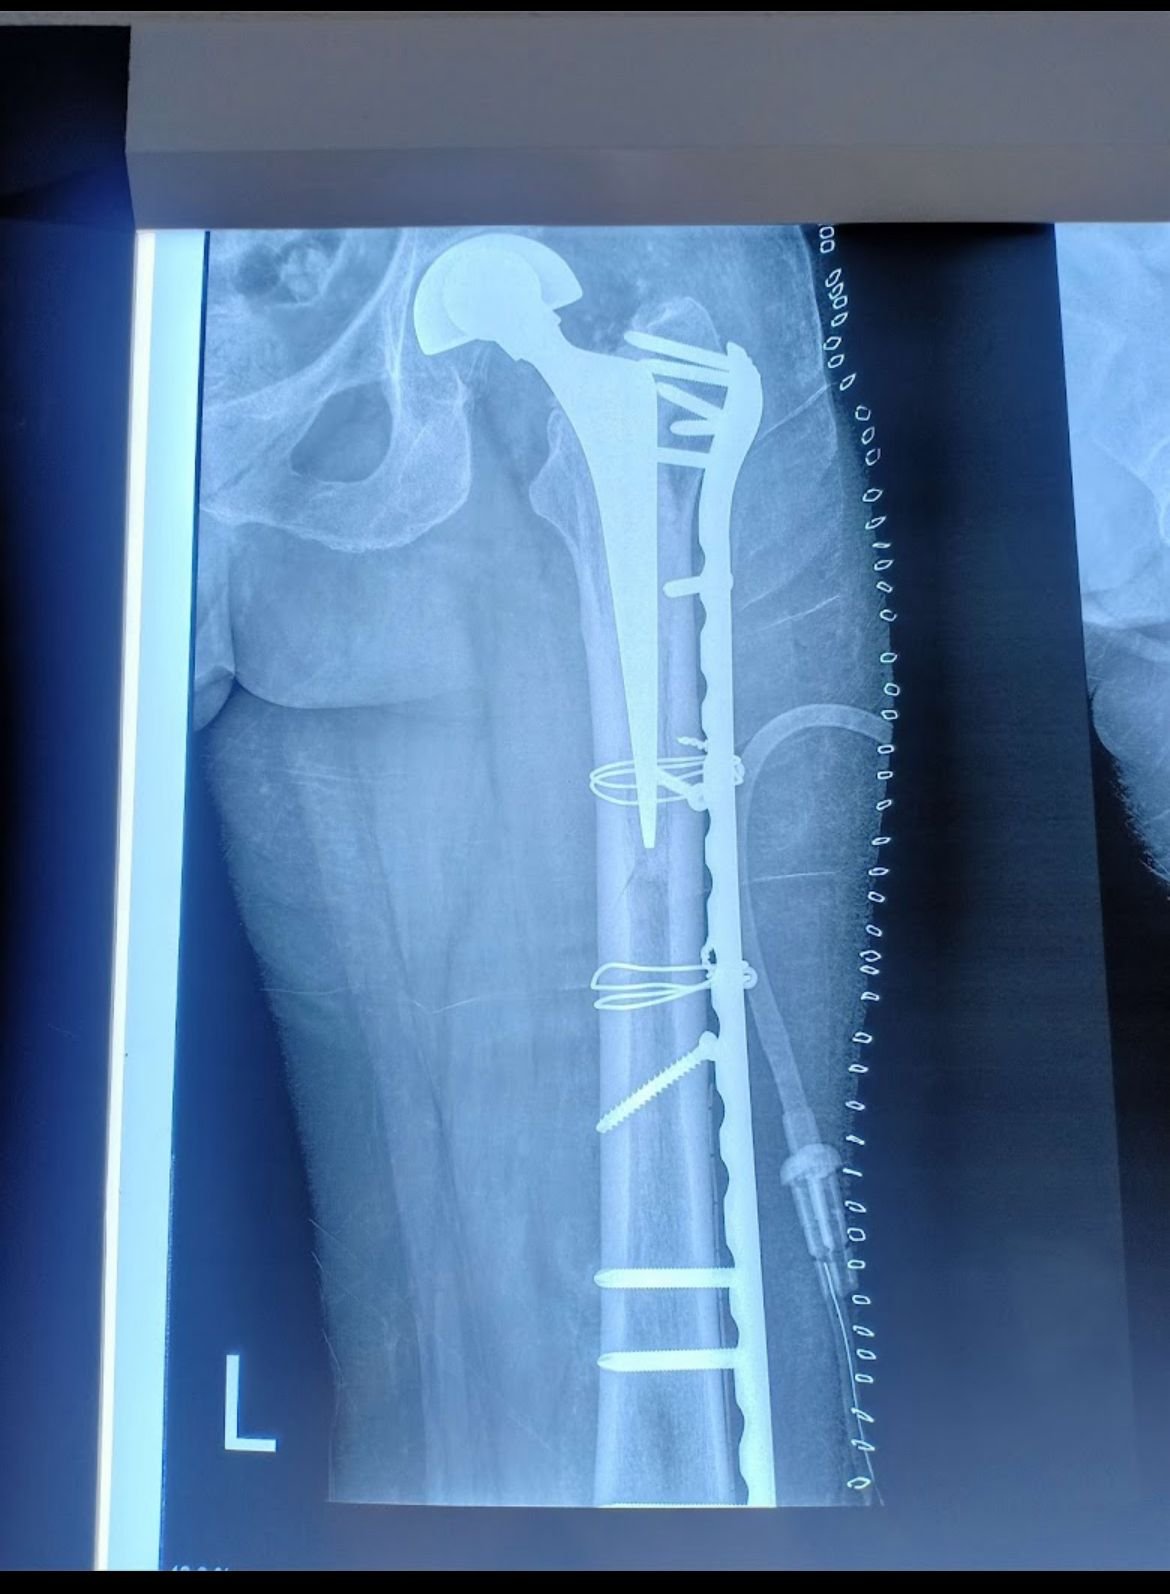

Hip Replacement

Knee Replacement

Limb Lengthening